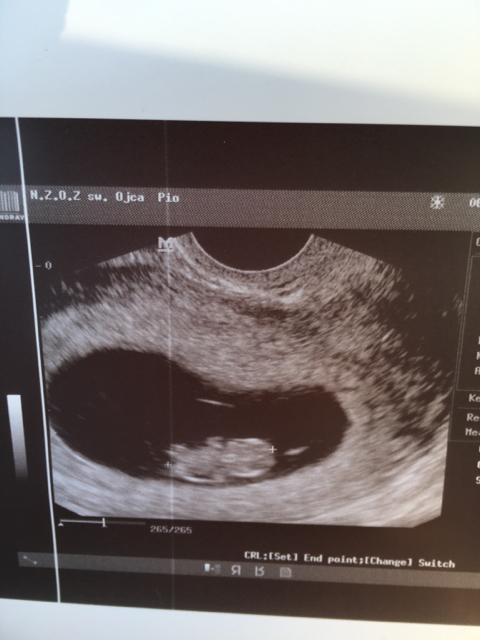

Wtedy byl chyba 9 plus 4 albo 5Który to tydzień??

Ciekawa jestem o ile będzie większe moje maleństwo jak pójdę we wtorek, bo to już będzie 10t2d mam nadzieję, że będzie i że nic złego się nie stało od ostatniej wizyty...Wg OM dzis rozpoczyna się 9 tydzień, a na USG napisane, że 8t5d, więc dużej różnicy nie ma